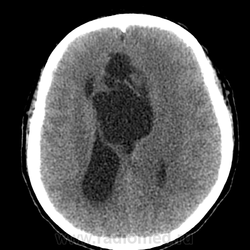

Действительно любопытно! Только сканов мало. Пока мысль о кисте полости межжелудочковой перегородки. Нет ли там где препятствия или изолированная киста?))

Может, это две межполушарные арахноидальные кисты?

Однозначно киста, значит, осталось выяснить какая, холестеатома или арахноидальная?